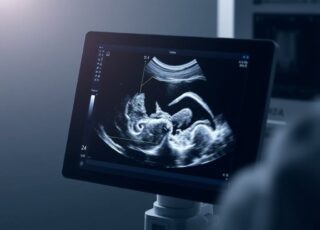

УЗИ: невидимая камера внутри нас, что можно увидеть и как подготовиться

Ультразвуковое исследование, или просто УЗИ, кажется знакомой процедурой: врач наносит гель, поводит датчиком, и на...